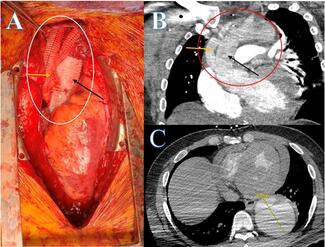

Craig Basman, MD; Ryan Kaple, MD; Sung-Han Yoon, MD; Vladimir Jelnin, MD; Jessica Willert, MD; Perry Wengrofsky, MD; George Stoupakis

The authors report their approach to managing a challenging case involving both a paravalvular leak and a large associated pseudoaneurysm, ensuring complete exclusion of both.

12/30/2024

Journal of Invasive Cardiology